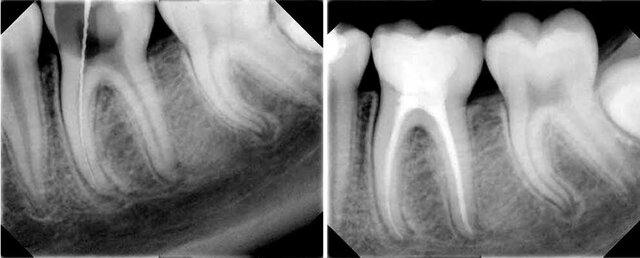

• Period: to

ÉPOCA DE LA TECNOLOGÍA EN ENDODONCIA

En los últimos años ha sido notoria la influencia que la tecnología ha tenido en la práctica de la endodoncia. A tal grado ha sido así que tanto las técnicas de procedimientos tan comunes como la conductometría, la preparación biomecánica como la obturación de los conductos tienen que ser reaprendidas por los endodoncistas veteranos puesto que la técnica ha introducido instrumental, aparatología y materiales novedosos.